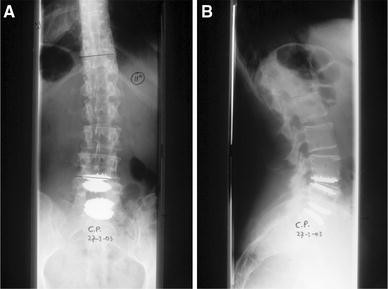

A pre- and post-operative radiograph of one case, in which we removed the disc prosthesis L4–5 and L5–S1 and performed a posterior and anterior fusion, is shown in Figs. 3 and 4.

Fig. 3

figure 3

a Anteroposterior and b lateral radiograph of the lumbar spine 3 years and 9 months after disc replacement at L4–5 and L5–S1

Fig. 4

figure 4

a Anteroposterior and b lateral radiograph of the lumbar spine 9 months after revison surgery